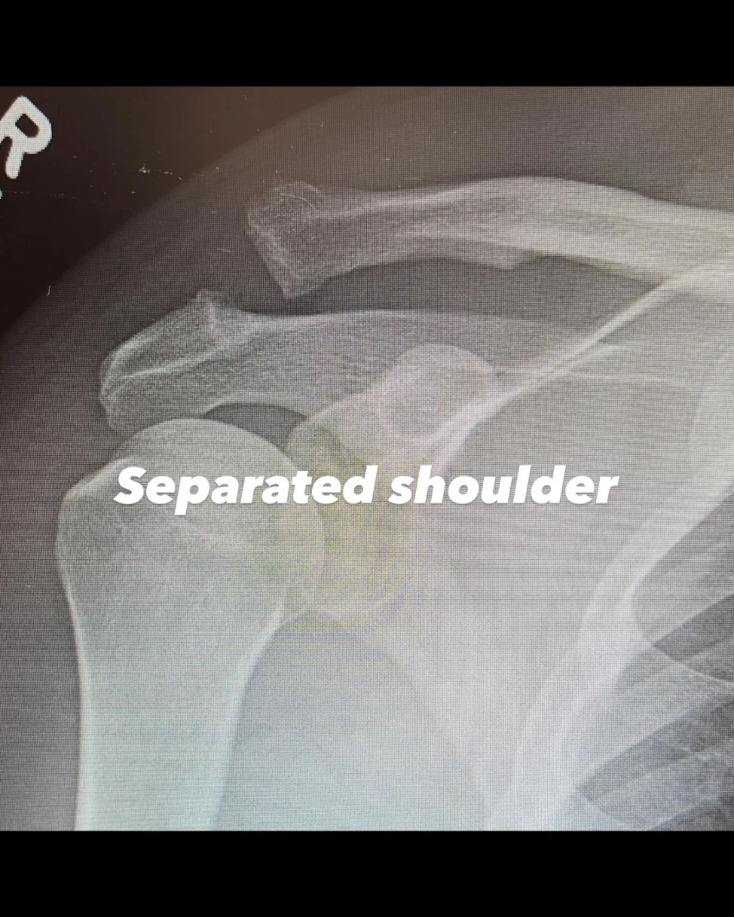

Ο Τσάνινγκ Τέιτουμ ανάρτησε μία φωτογραφία με ακτινογραφία του άνω βραχίονα και της περιοχής του ώμου, στην οποία φαινόταν ότι είχαν σπάσει δύο οστά

Ο ηθοποιός ανάρτησε μία φωτογραφία με ακτινογραφία του άνω βραχίονα και της περιοχής του ώμου, στην οποία φαινόταν ότι είχαν σπάσει δύο οστά. «Εξάρθρωση ώμου», σχολίασε. «Βιδωμένος ώμος. Γιούπι», ανέφερε στη λεζάντα της επόμενης ακτινογραφίας, στην οποία διακρίνεται πλέον μια μεγάλη βίδα που συγκρατεί τα οστά στη θέση τους.